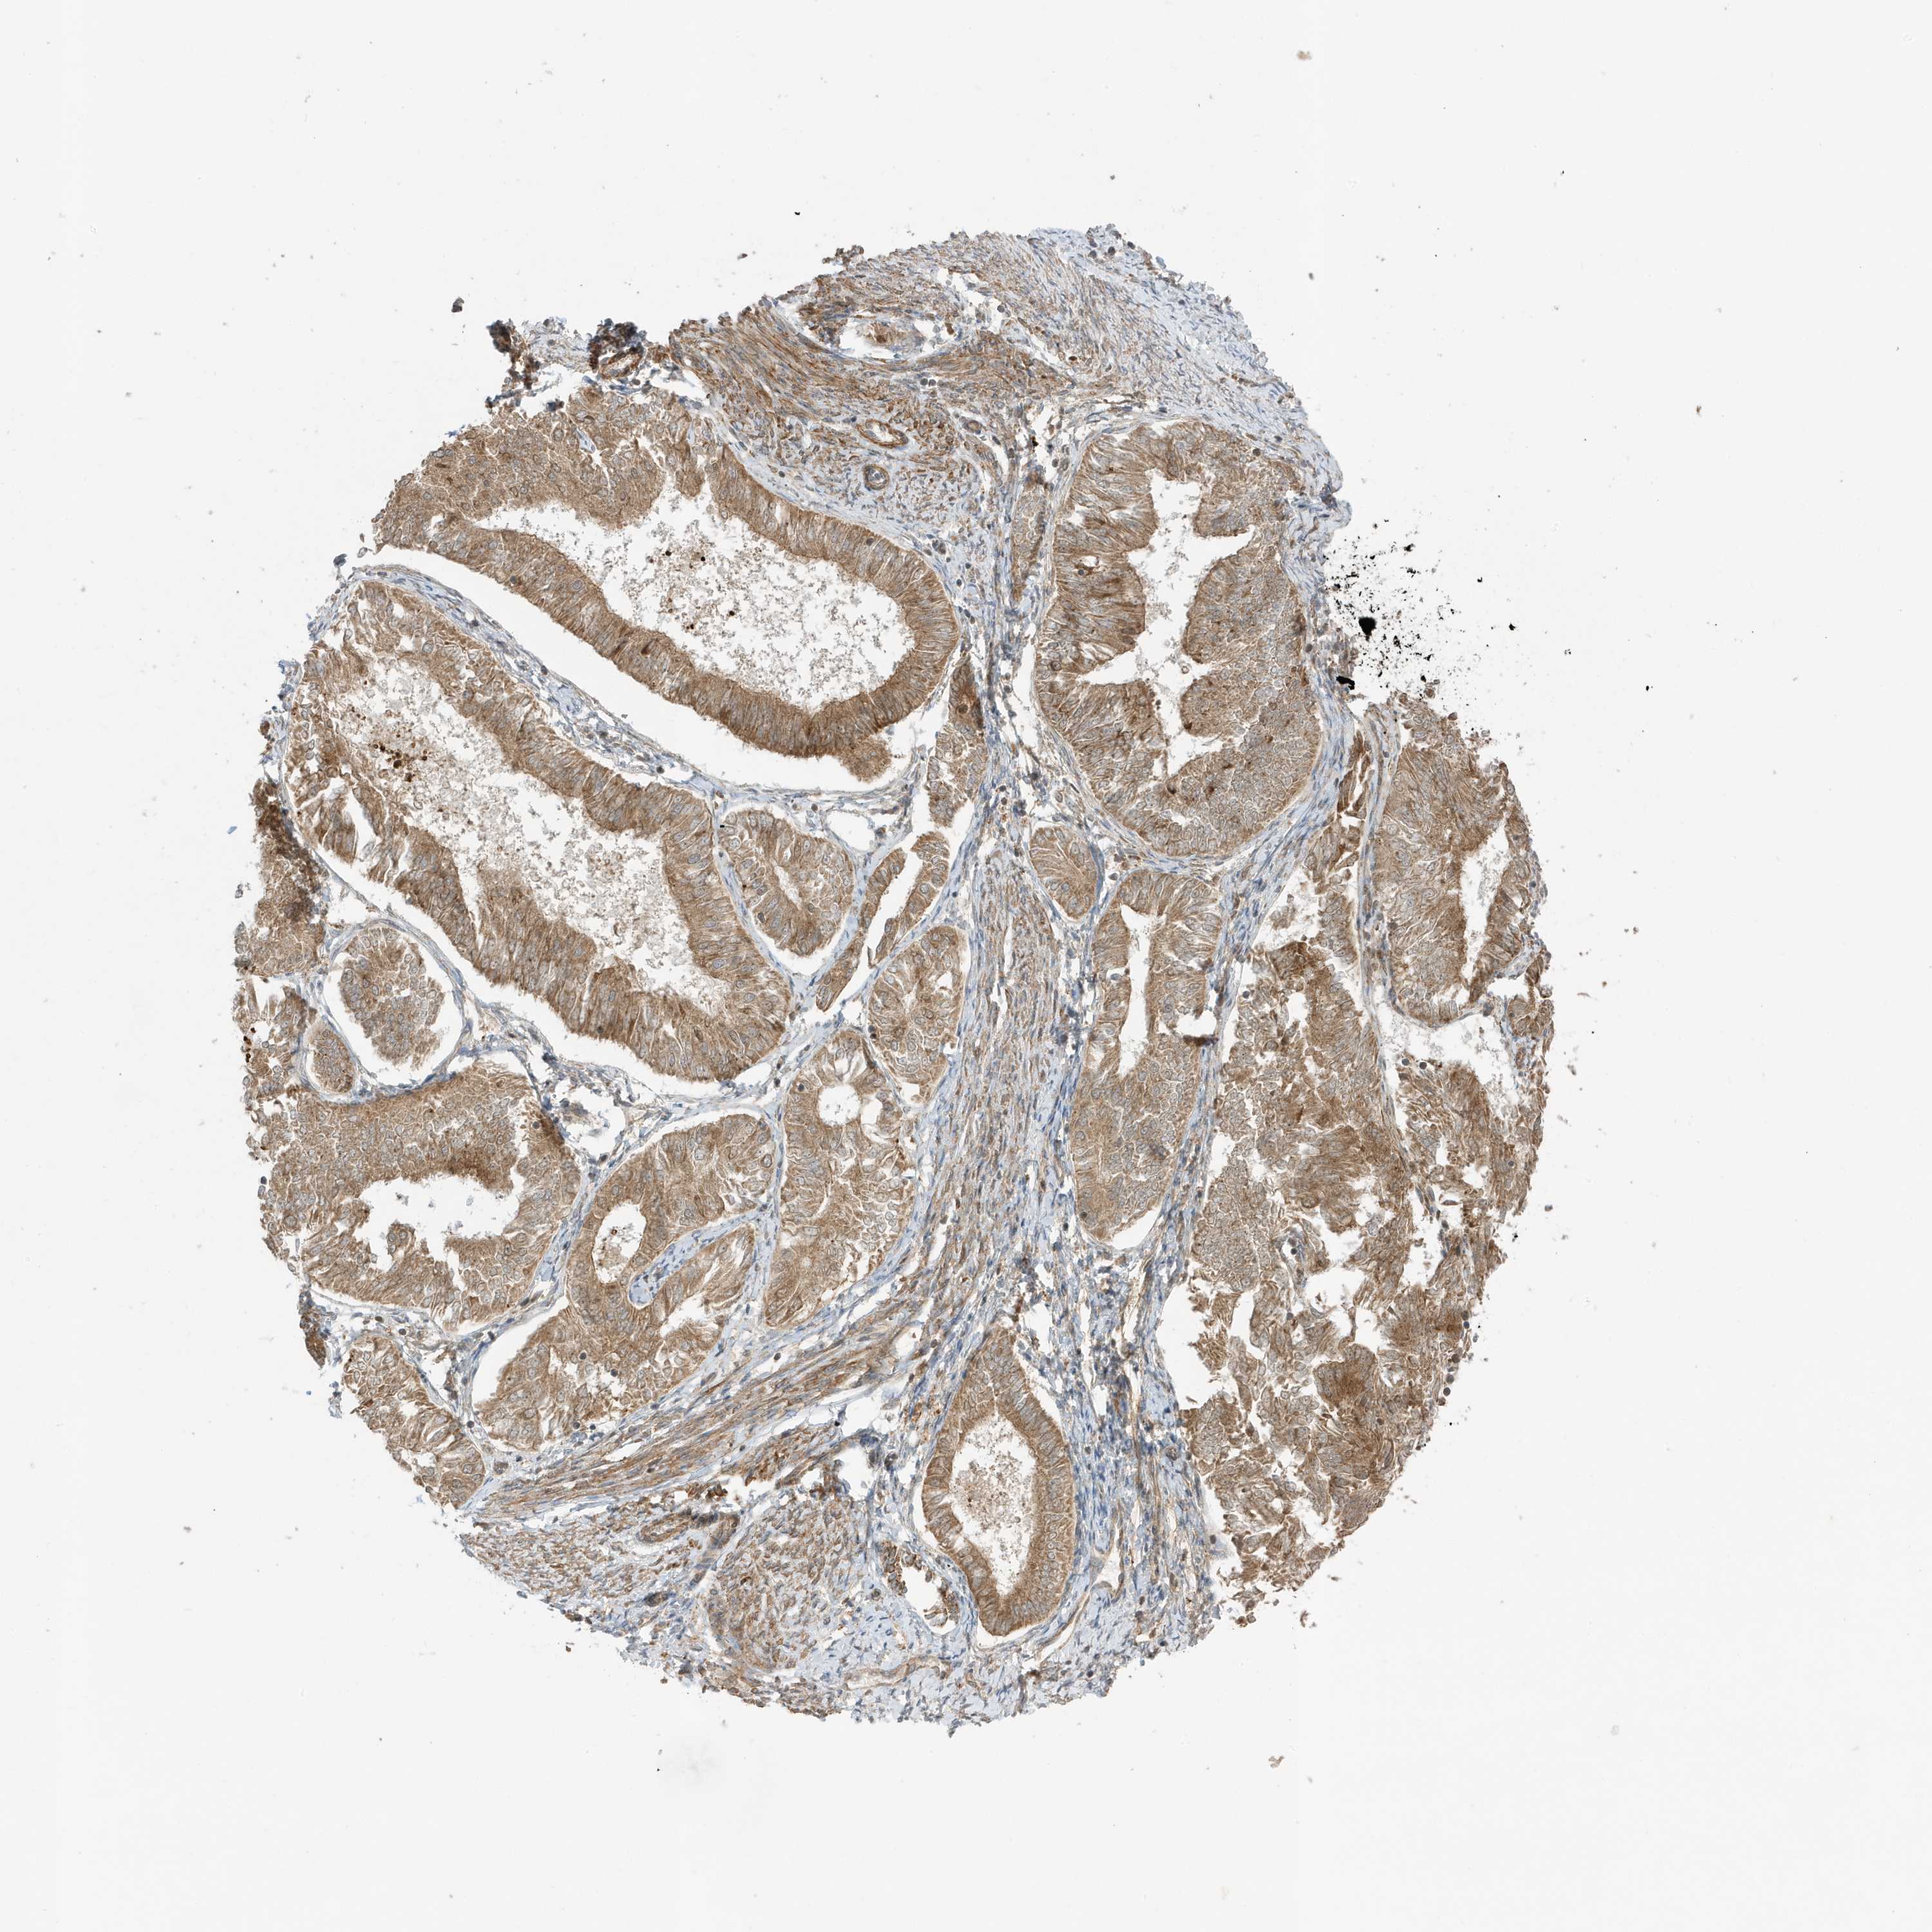

ENDOMETRIAL CANCER - Protein expressioni

A mouse-over function shows sample information and annotation data. Click on an image to view it in a full screen mode. Samples can be filtered based on level of antibody staining by selecting one or several of the following categories: high, medium, low and not detected. The assay and annotation is described here.

Note that samples used for immunohistochemistry by the Human Protein Atlas do not correspond to samples in the TCGA dataset.

Antibody stainingi

Antibody staining in the annotated cell types in the current human tissue is reported as not detected, low, medium, or high, based on conventional immunohistochemistry profiling in selected tissues. This score is based on the combination of the staining intensity and fraction of stained cells.

Each image is clickable and will lead to virtual microscopy that enables deeper exploration of all samples and also displays staining intensity scores, fraction scores and subcellular localization as well as patient and tissue information for each sample.

Antibody HPA035399

Staining

High

Medium

Low

Not detected

Intensity

Strong

Moderate

Weak

Negative

Quantity

>75%

75%-25%

<25%

None

Location

Nuclear

Cytoplasmic/membranous

Cytoplasmic/membranous,nuclear

Adenocarcinoma, NOS

Adenocarcinoma, metastatic, NOS